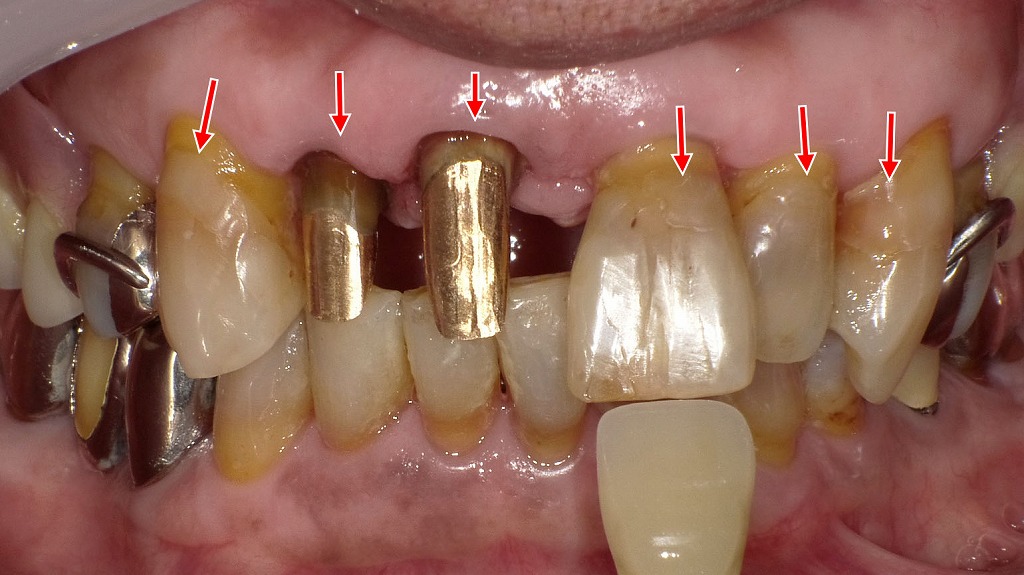

歯頚部う蝕へのレジン修復と前歯部コアの再構築✨

同症例に対し、歯頚部に認められたう蝕をコンポジットレジンにて充填修復しました。また、上顎1・2番には白金加金コアを装着し、歯根部の強度確保と適切な補綴前処置を行っています。歯頚部の清掃性と適合性を改善することで、二次う蝕や歯肉トラブルのリスク低減を図った治療例です。